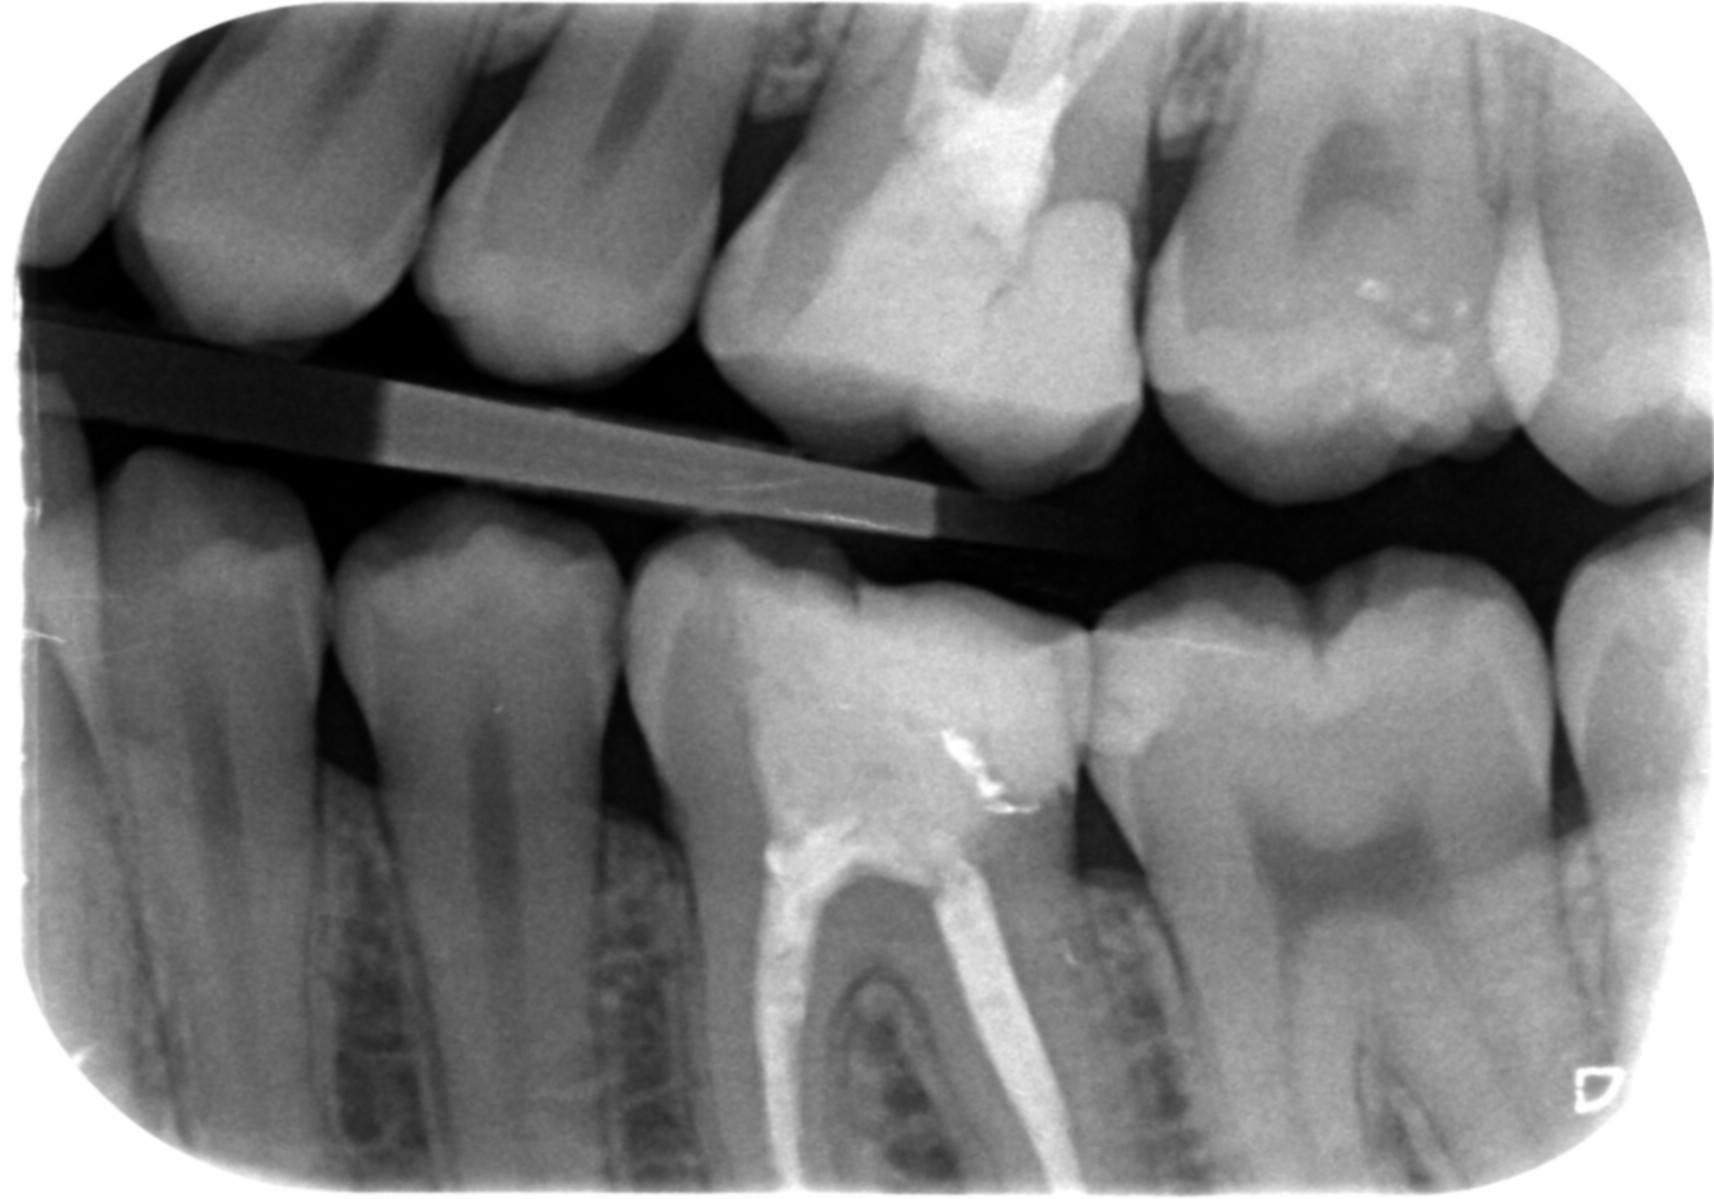

Er is best wat aan de hand, ook oudere vullingen voor verbetering vatbaar, maar dat hoeft niet allemaal nu en op korte termijn.

Endo``s zien er goed uit, wat geen garantie is dat er geen problemen mee zijn of komen. beeld op foto is het enige waar ik op kan oordelen , dat zegt ook niet alles.

de 27, 37, 35, 17,16,47,46, 44 en 45 hebben wat mij betreft de prioriteit, die zou ik niet op te lange termijn doen. MN de 46 is een lastige en kritische plek, daar te laat ingrijpen kan verlies kies betekenen.